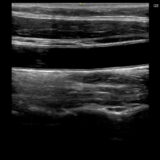

- 甲状腺エコー

- 頸動脈エコー

- 下肢静脈エコー(深部・表在)

- 下肢動脈エコー(整形外科・フットケア領域向け)